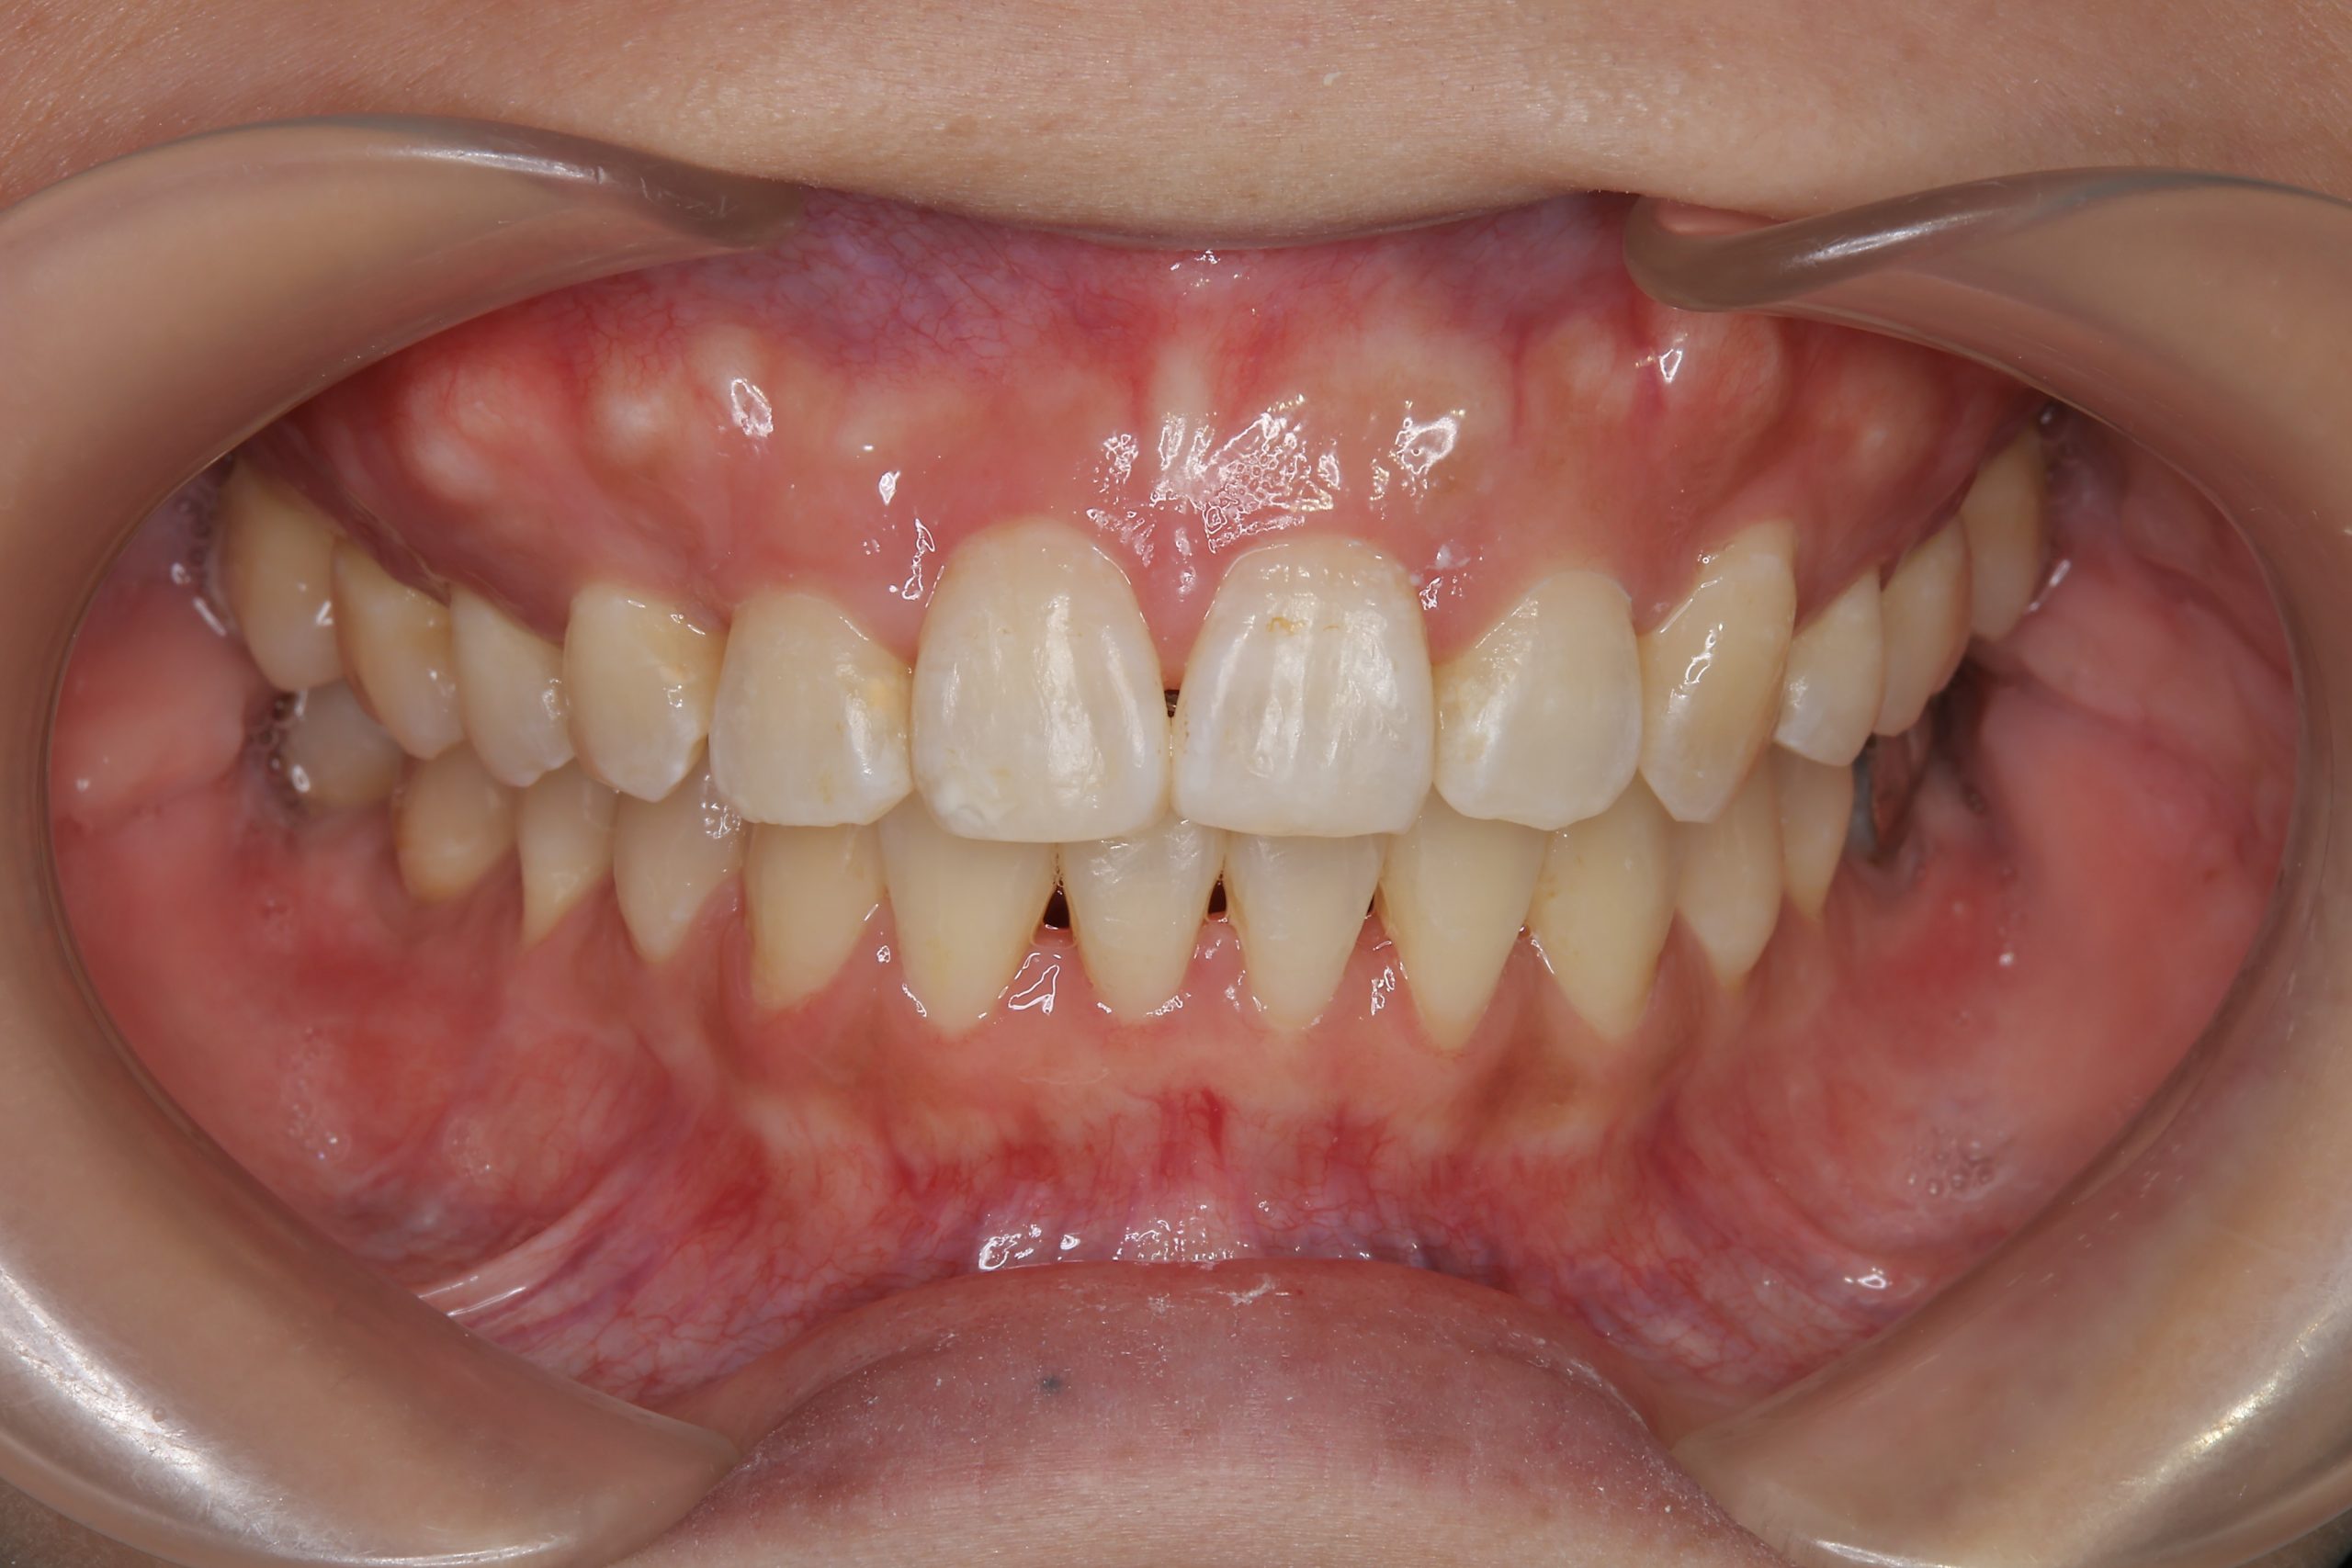

アフター

主訴 八重歯

施術内容 MSEと下顎リンガルアーチを用いて上下顎骨を拡大した。

その後上顎3・4番を抜歯しマルチブラケット装置とミニインプラントを用いて

歯牙を配列した。良好な咬合を獲得した。

治癒期間 1年8か月間